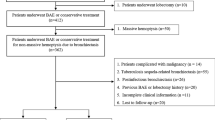

This single-centre retrospective study included 57 consecutive patients who underwent 2nd series ssBACE for the management of recurrent haemoptysis after 1st series elective ssBACE (n = 489) at our institution between April 2010 and December 2015 [16]. As previously reported, we defined haemoptysis and recurrent haemoptysis as airway bleeding with an estimated volume of greater than 20 cm3. In this study, ssBACE was indicated for patients with severe impairments to daily quality of life regardless of the amount of haemoptysis [16]. We collected data on all the variables shown in tables and figures retrospectively from the patient records. In the present study, underlying diseases included bronchiectasis, NTM pulmonary infection, pulmonary aspergillosis, pulmonary tuberculosis (Tb) sequelae and cryptogenic haemoptysis. Exacerbation of underlying diseases was evaluated by the consensus of two pulmonologists on the basis of CT findings. We defined exacerbation as being present when the number or extent of disease-related findings increased in the lung parenchyma on CT at 2nd series ssBACE compared with the findings at 1st series ssBACE. For example, exacerbation of bronchiectasis was determined if new enlargement or increase of dilated bronchus was present. Decision was withheld if the presence of blood significantly impaired accurate interpretation by masking lung parenchymal changes because of exacerbation of underlying diseases (n = 1). The study protocol complied with the standards outlined in the Declaration of Helsinki and was approved by the institutional ethical committee (approval number 2017-03). The requirement of written informed consent was waived because of the retrospective nature of the study. Several cases have previously been published as image-content sharing case reports in another journal [18].

The mechanisms of recurrent haemoptysis are shown in Fig. 2 and Table 2. In general, recanalisation (45.2%) of HRAs was the most common cause in patients with recurrent haemoptysis, followed by new HRA (38.5%), bridging collaterals (14.7%) and conventional collaterals (1.7%) (Fig. 2A). We have presented representative cases with recanalisation and bridging collaterals in Fig. 3 for reference. In a retrospective review of all new HRAs, four could be identified using e-CT evaluation at the 1st series ssBACE. The new HRA category includes the vessels that were overlooked (n = 4) or ones that could not be embolised (n = 3) at the time of the 1st series ssBACE. Several subsets of patients, such as those with no exacerbation of underlying disease (Fig. 2B) and those receiving an anticoagulant (Fig. 2C) or antiplatelet agent (Fig. 2D), showed statistically significant different trends.